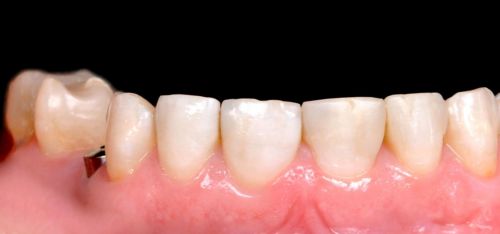

Wykonana praca protetyczna:

- licówki pełnoceramiczne w odcinku przednim zębów górnych

- korony pełnoceramiczne na zęby własne zarówno w łuku dolnym i górnym

- korony na implantach braków zębów